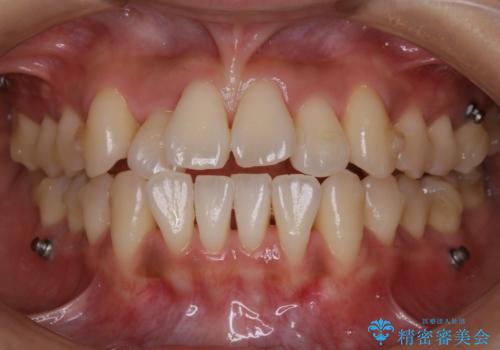

【非抜歯】左右の八重歯・前歯の反対咬合の改善 インビザライン

- 前歯のガタつきを主訴にご来院されました。

診査の結果、骨の厚みに余裕がなく幅の拡大とIPR(歯と歯の間を削り隙間を作る作業)のみでは歯周病に対する不安が残ることが懸念されたため、マイクロインプラントを用いて奥歯から順にすべての歯を後方移動させる方法によってスペースを作ることとなりました。